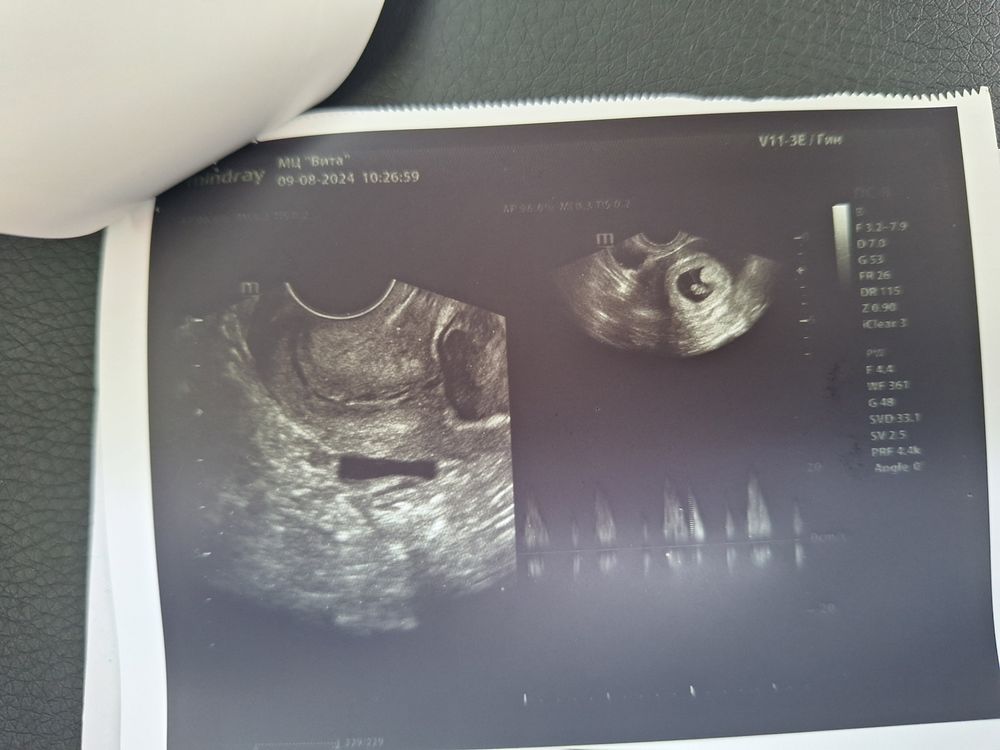

Мы 11 мм. СБ 155

Мы развиваемся! Гемотома большая!